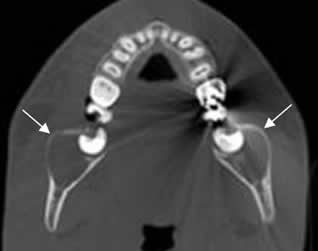

TAC axial. Quistes dentígeros bilaterales, en relación con las raíces dentales.

Fig 62. Quiste dentígero.

A: Panorámica de dentascan y TAC reconstrucción transversal. Molar incluido y horizontalizado, (Flecha gruesa) con lesión quística, excéntrica y en relación con la corona. (Flechas delgadas).